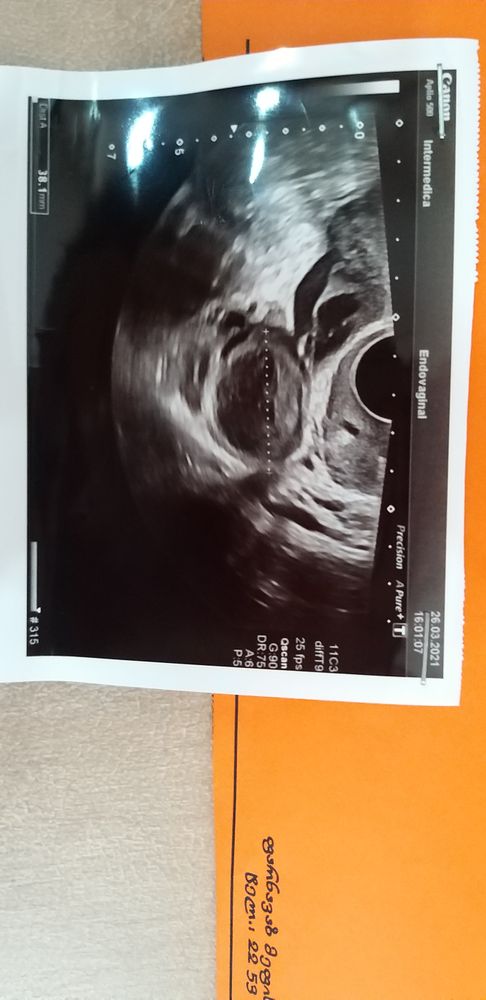

Я уже писала, что позавчера на 13 дц по УЗИ в левом яичнике ДФ 2,22 см. Пошла сегодня, на 15 дц, посмотреть, случилась ли О, а врач говорит у вас в ЛЯ киста ЖТ, размер 3,81 см, но при этом нет жидкости в малом тазу. Вот и возник вопрос: если нет жидкости, значит О не случилась, но почему тогда киста ЖТ? Ведь ЖТ или киста ЖТ образуется после овуляции.

Как такое может быть? Может быть ошибка УЗИ?🤦♀️